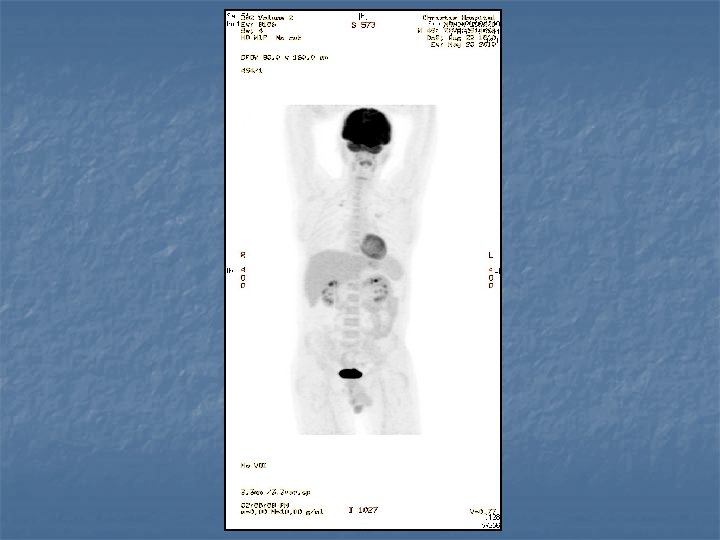

n n n PRETREATMENT INVESTIGATIONS: FBC, Renal and liver function, LDH, urate, Ig. GS. Histology review. Marrow aspirate+trephine (cytogenetics, immunology) CD 4 , HIV viral load. CT Scans. (MR Brain) (PET scan ) Echo / LVEF CMV, Hep B+C, Toxoplasma serology MAI screen. LP for CSF cytology +/- intrathecal Rx. (DLBC , Burkitt, Plasmablastic).